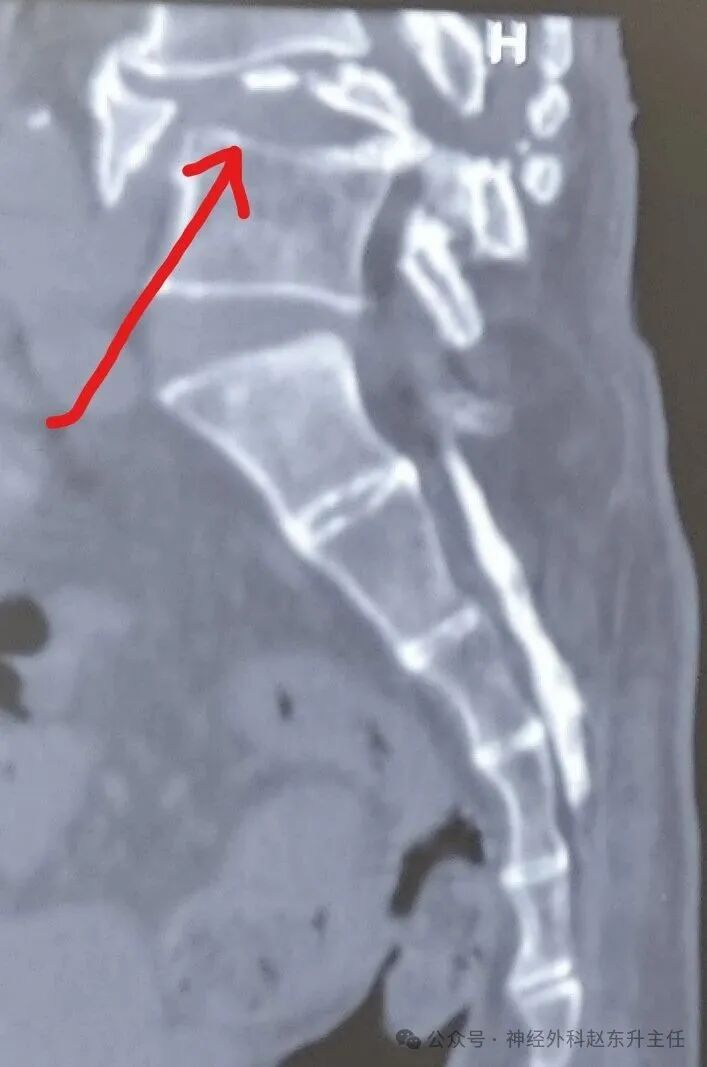

2.jpg腰椎CT提示腰椎滑脱伴骨折